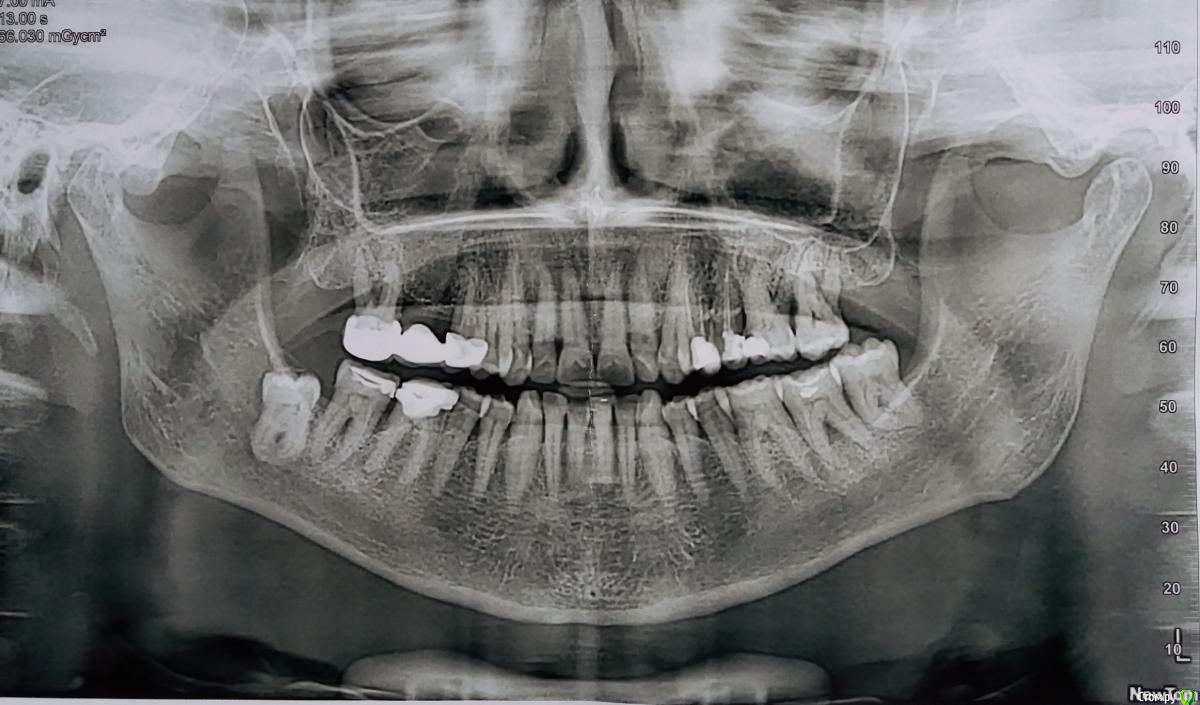

pauleta Опубликовано 4 марта, 2019 Поделиться Опубликовано 4 марта, 2019 (изменено) Здравствуйте! Обратилась к пародонтологу для проведения профессиональной чистки зубов. Кроме этого, она настаивает на проведении операции. Уважаемые профессионалы, пожалуйста, ваше мнение, действительно ли имеются показания к оперативному вмешательство в каком-либо сегменте? Изменено 4 марта, 2019 пользователем pauleta Ссылка на комментарий

pauleta Опубликовано 4 марта, 2019 Автор Поделиться Опубликовано 4 марта, 2019 Какой? Хорошо, в частности, доктору не нравится бифуркационная зона в районе 37 зуба. Ссылка на комментарий

Bier Опубликовано 6 марта, 2019 Поделиться Опубликовано 6 марта, 2019 у вас есть явления пародонтита, они по большей части связаны с несовершенными пломбами на зубах. Нужно сделать нормальные реставрации для начала. Ссылка на комментарий

Nazim_NV86 Опубликовано 7 марта, 2019 Поделиться Опубликовано 7 марта, 2019 Понятно? Т. е. вы также полагаете, что это проблемная зона? Пожалуйста, поделитесь соображения.Не только на 37. Имеются пародонтальные карманы и скорее всего док советует сделать открытый кюретаж. Ссылка на комментарий